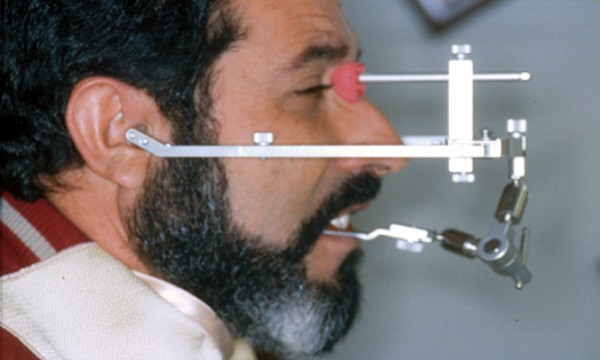

Bio Pack

Fig.6

Sensores Electromiográficos

Bio Pack

Fig.7

Receptor electromiográfico

Bio Pack

Fig.8

Magneto detector del

Movimiento

Bio Pack

Fig.9

Bobinas captoras del

Movimiento del magneto